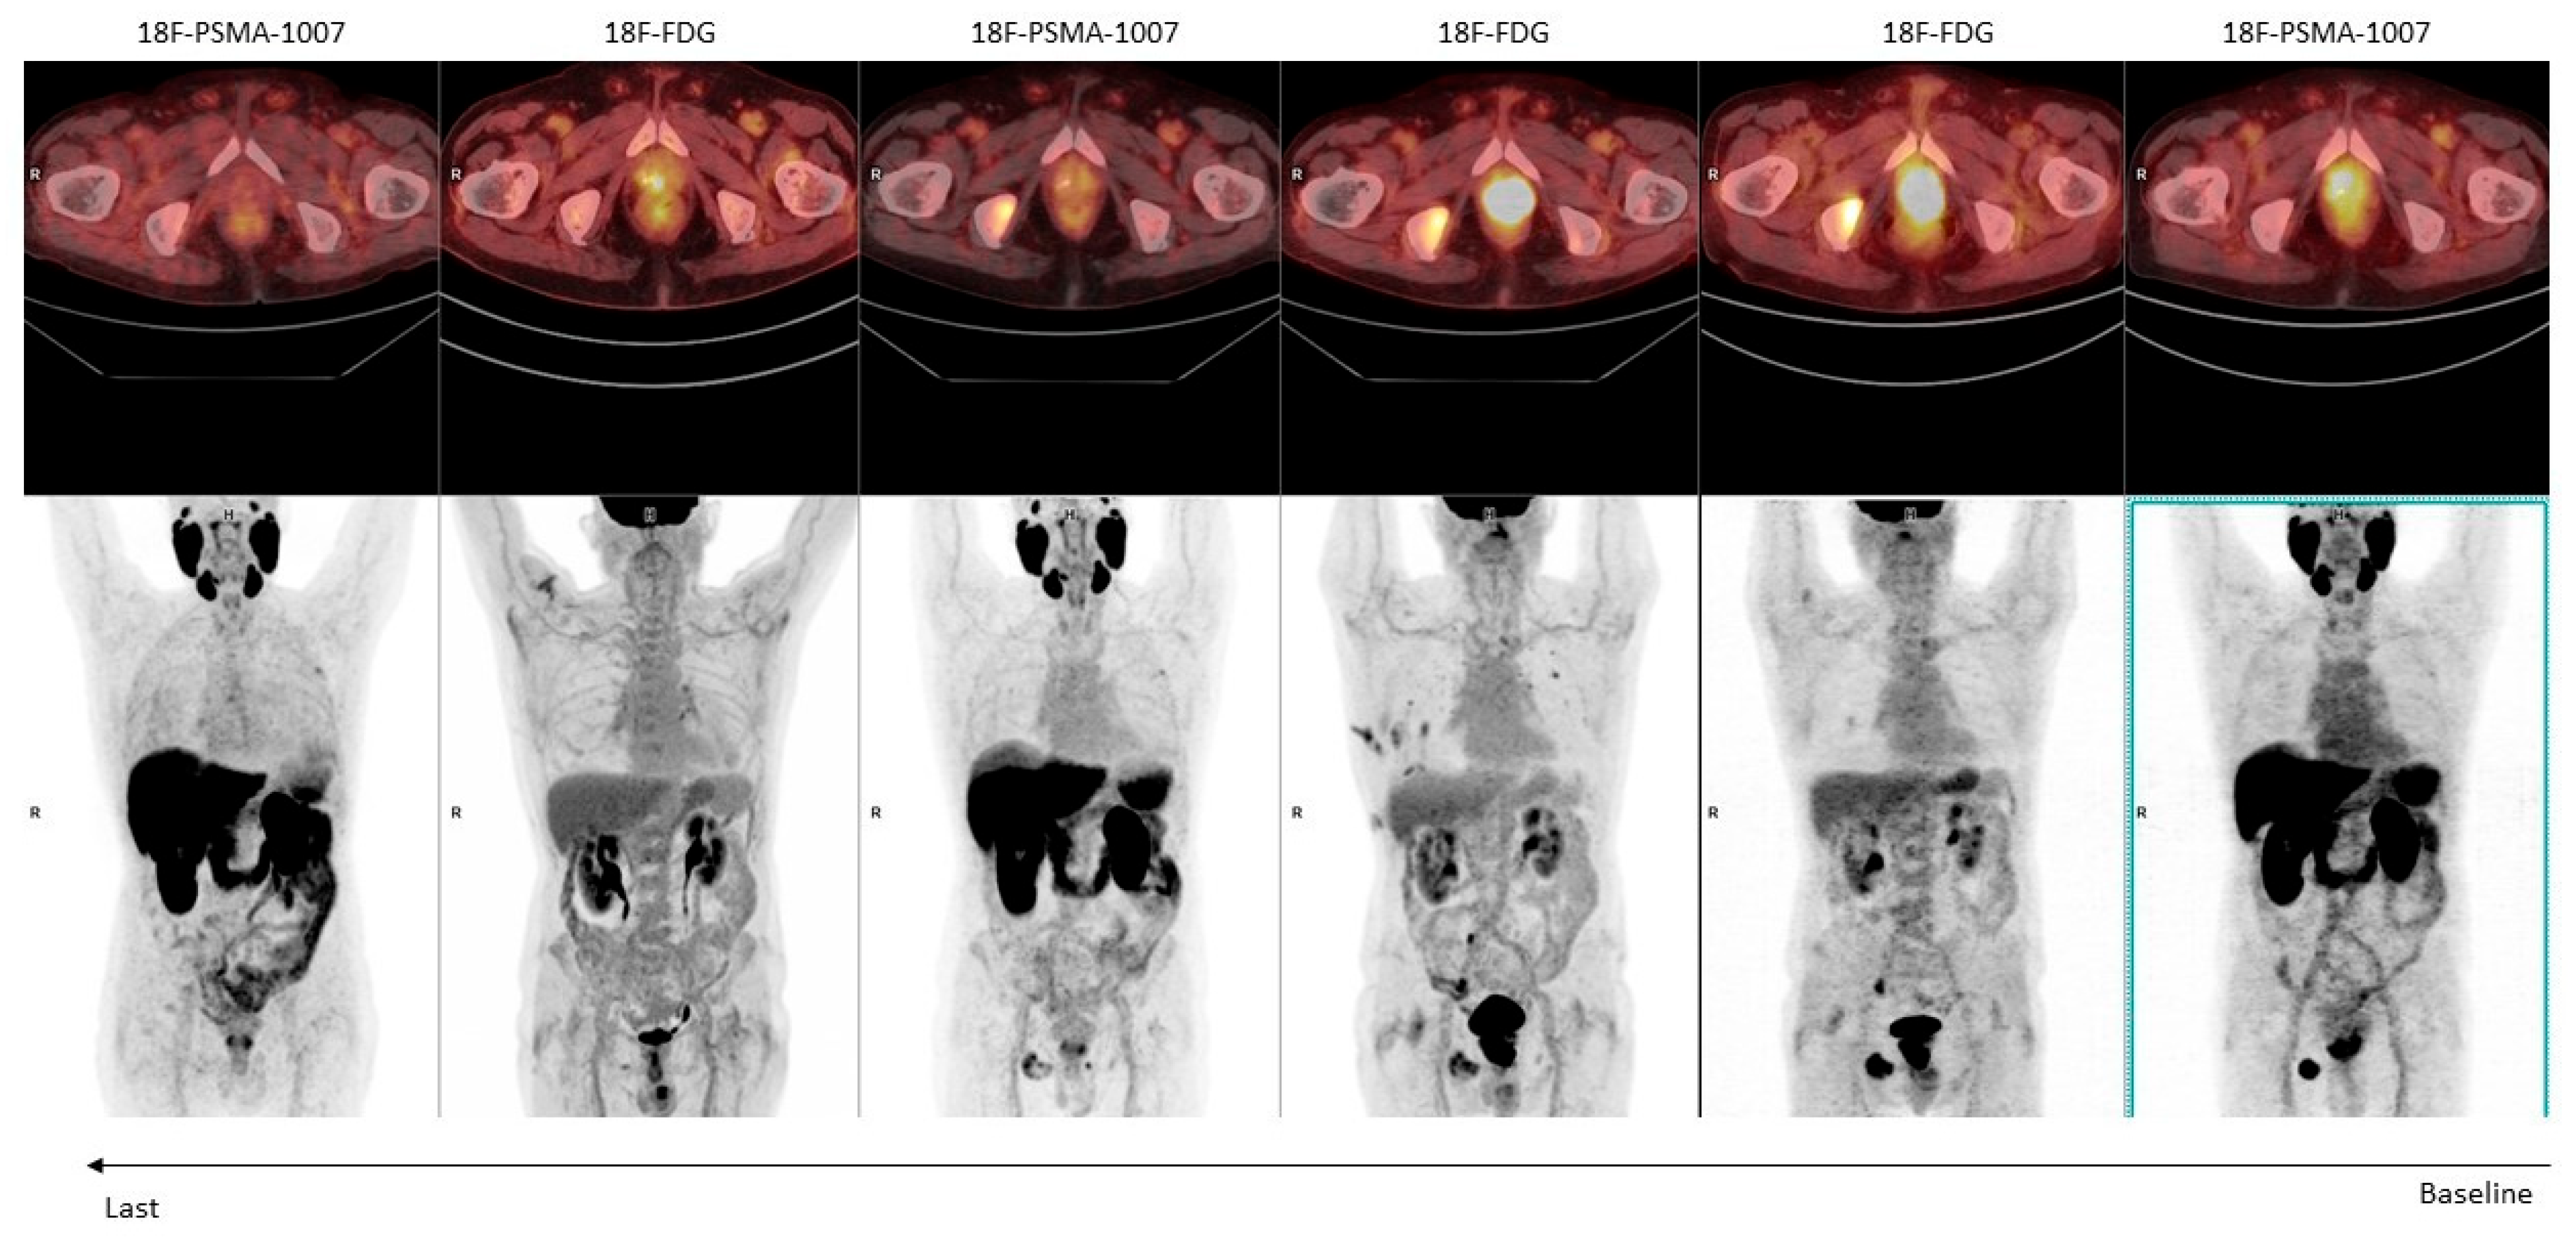

3.3. Dual-Tracer PSMA/18F-FDG: Is It a Must?

- Seifert, R.; Telli, T.; Hadaschik, B.; Fendler, W.P.; Kuo, P.H.; Herrmann, K. Is 18F-FDG PET Needed to Assess 177Lu-PSMA Therapy Eligibility? A VISION-like, Single-Center Analysis. J. Nucl. Med. 2023, 64, 731–737. [Google Scholar] [CrossRef]

- Chen, R.; Wang, Y.; Zhu, Y.; Shi, Y.; Xu, L.; Huang, G.; Liu, J. The Added Value of 18F-FDG PET/CT Compared with 68Ga-PSMA PET/CT in Patients with Castration-Resistant Prostate Cancer. J. Nucl. Med. 2022, 63, 69–75. [Google Scholar] [CrossRef]

| Michalski et al. [48] | Germany 2021 | Retrospective bicenter | 54 | Assessment of mismatched lesions in mCRPC patients before RLT. | [68Ga]-PSMA-11 [18F]FDG | 33% of mCRPC patients show mismatched PSMA- [18F]FDG+ lesions and these patients present shorter OS. |

| Seifert et al. [30] | Germany, USA 2022 | Retrospective | 89 | Assessment of mismatched lesions in mCRPC patients before RLT. | [68Ga]-PSMA-11 [18F]-PSMA-1007 [18F]FDG | 18% of patients had mismatched lesions between PSMA and [18F]FDG PET, however only 3% of patients had mismatch findings not detected using only PSMA PET. |

| Chen et al. [42] | China 2022 | Retrospective | 56 | To assess metabolic heterogeneity of mCRPC patients | [68Ga]-PSMA-11 [18F]FDG | [68Ga]-PSMA-11 PET/CT showed higher detection rate than [18F]FDG PET/CT (75% vs. 51.8%). However, 23.2% of patients showed at least 1 mismatched PSMA- [18F]FDG+ lesion. |

| Güzel et al. [49] | Turkey 2023 | Retrospective | 71 | To investigate the prognostic role of dual-tracer PET imaging in [18F]FDG+ mCRPC treated with chemotherapy | 68Ga-PSMA-11 [18F]FDG | Volumetric parameters and Pro-PET scores obtained from dual-tracer PET/CT imaging predict OS in patients with mCRPC treated with taxane chemotherapy. Dual-tracer imaging should be performed in these patients as 78.9% of visceral metastases were PSMA−/FDG+ |